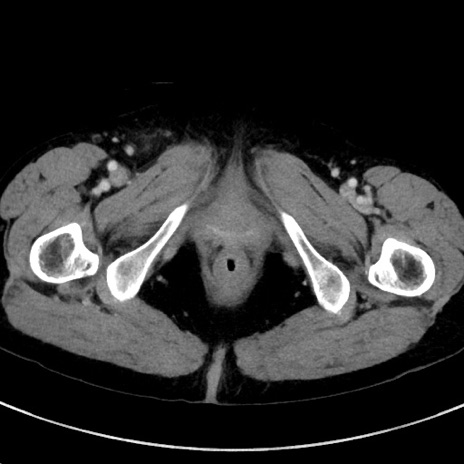

症例23(横断像)

【症例】70歳代女性

【主訴】下腹部痛・嘔吐

【現病歴】2日前より腹痛あり。昨日嘔吐あり。症状改善しないため来院。

【既往歴】胃GISTに対して胃部分切除後。

【身体所見】BT 37.1℃、BP 128/77mmHg、腹部:平坦・軟、下腹部に圧痛あり。

【データ】WBC 10200、CRP 0.31